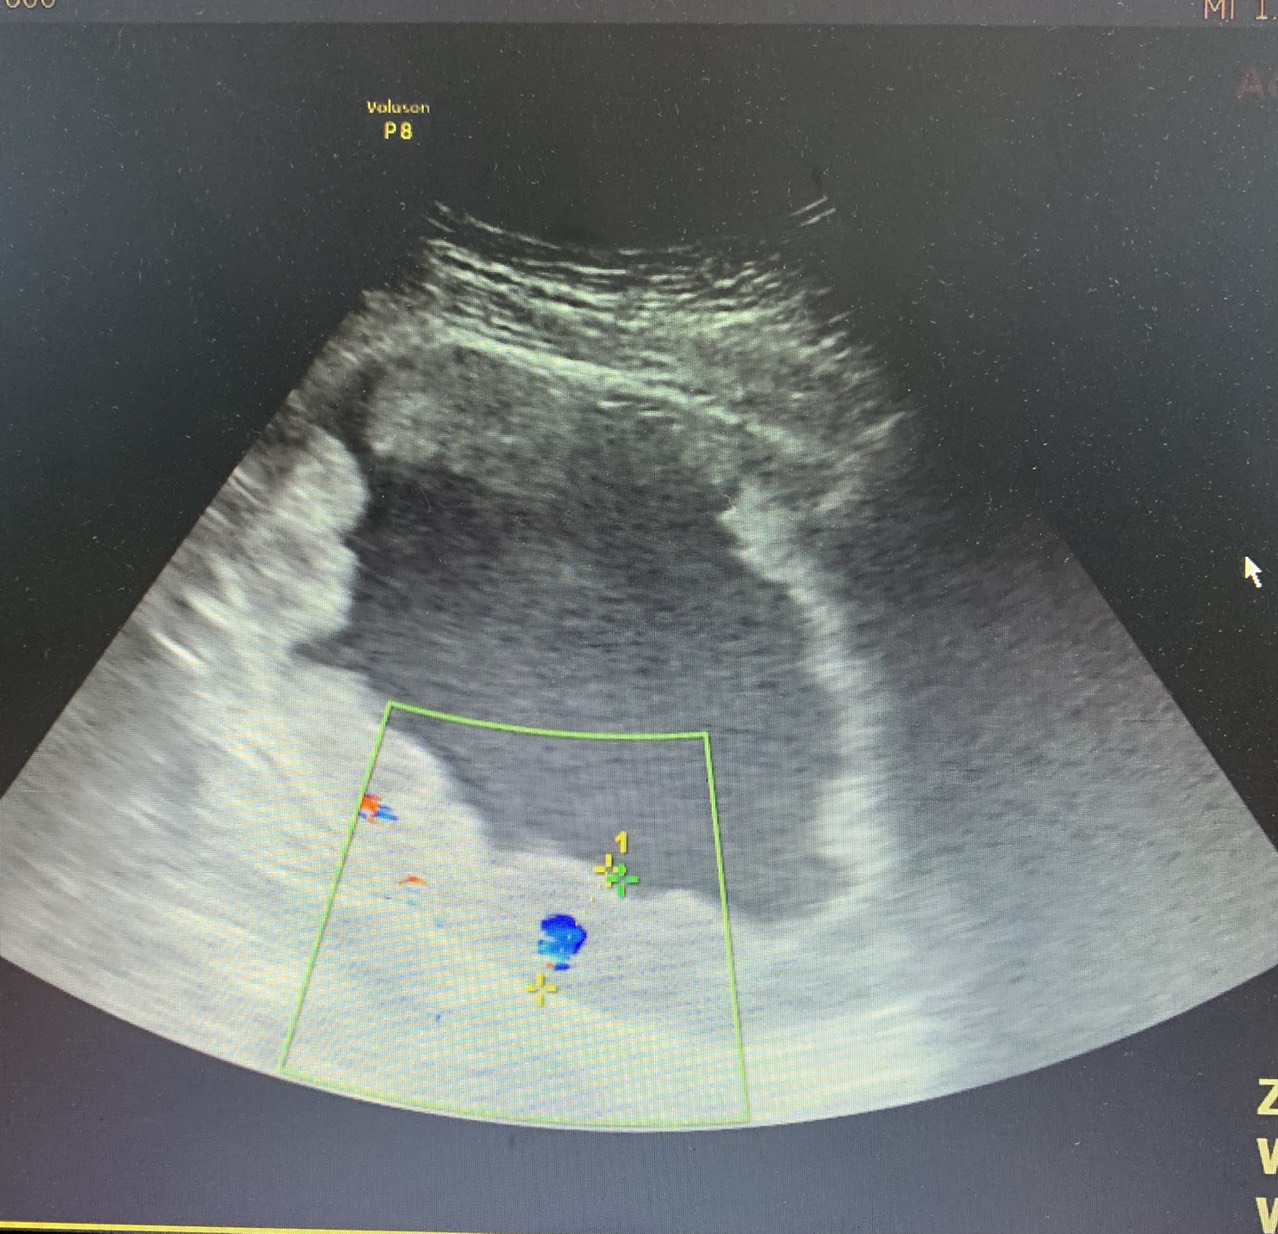

Bệnh nhân nam 69 tuổi, ở Vĩnh Niệm, Lê Chân, Hải Phòng có tiền sử tán sỏi bàng quang, đau bụng âm ỉ vùng hạ vị – hố chậu 2 bên khoảng 1 tháng trước vào viện, đôi khi có cảm giác đau vùng hạ vị tăng lên khi đi tiểu, đái máu, đái buốt, rắt và đái ít dần. Bệnh nhân mệt mỏi, chán ăn, đầy chướng bụng và đến khám tại Bệnh viện đa khoa Quốc tế Hải Phòng. Qua thăm khám và làm các xét nghiệm cận lâm sàng cần thiết, các bác sĩ phát hiện hình ảnh u bàng quang đa ổ rải rác khắp toàn bộ bàng quang, phát triển sâu vào lớp cơ bàng quang, xâm lấn lỗ niệu quản 2 bên, gây giãn niệu quản và bể thận 2 bên làm cho bệnh nhân bị suy thận. Kết quả giải phẫu bệnh là ung thư biểu mô đường niệu chuyển tiếp thể nhú.

Đứng trước bệnh nhân có tình trạng bệnh lý nặng kèm nhiều bệnh phối hợp như: suy thận, tăng huyết áp, đái tháo đường type 2, có nhiều polyp trực tràng, các bác sĩ Khoa Ngoại thận tiết niệu – Nam học, Bệnh viện đa khoa Quốc tế Hải Phòng quyết định phẫu thuật cắt toàn bộ bàng quang, túi tinh, tuyến tiền liệt, nạo vét hạch 2 bên, chuyển lưu nước tiểu theo phương pháp Bricker nhằm điều trị triệt căn ung thư, nâng cao chất lượng sống cho bệnh nhân. Ca phẫu thuật kéo dài 6 giờ đồng hồ được thực hiện thành công, sau mổ bệnh nhân tỉnh táo, tình trạng sức khỏe tiến triển tốt, ung thư được triệt căn hoàn toàn.